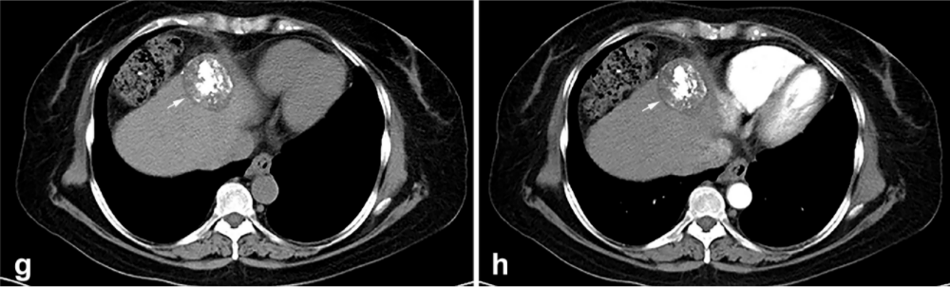

② 冷凍消融后 1 個(gè)月患者的增強(qiáng) CT 顯示HCC獲得緩解。

③ 總生存曲線和局部腫瘤進(jìn)展曲線:冷凍消融后中位生存時(shí)間為 27.3 個(gè)月,中位局部腫瘤進(jìn)展時(shí)間為 20.9 個(gè)月。